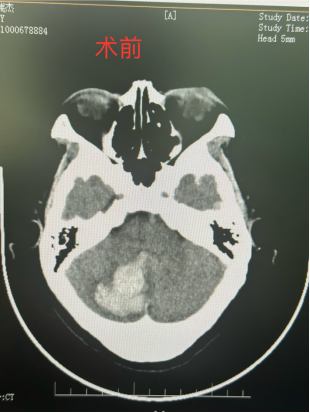

近日,我院接诊到一位因走路时不慎摔伤头部的患者,急诊科医护人员通知家属后立即开通绿色通道陪同患者完善CT检查,我院创伤医疗团队同时至CT室等待。徐学敏科主任明确目前诊断为创伤性小脑血肿,目前患者病情危重需急诊行神经内镜下颅内血肿清除术,完善术前准备后,立即送入手术室。

手术时间约2小时,术后患者恢复顺利,生命体征平稳,术后复查颅脑CT,小脑区域血肿已基本全部清除。